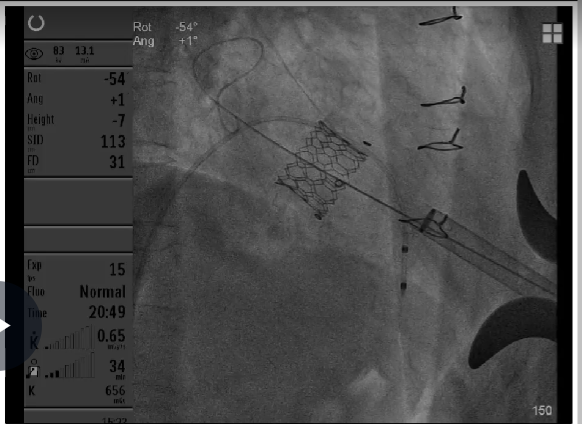

25#Renatus瓣膜释放

Atlas Gold球囊高压力后扩,扩断25#Mosaic瓣膜

瓣膜释放后状态

第一次高压球扩后形态

第二次高压球扩后形态